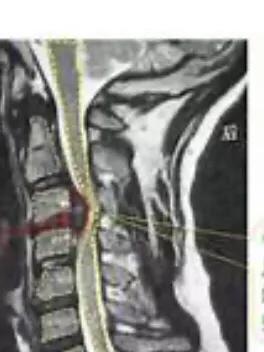

二,周围神经障碍引起的走路不穏:中毒代谢性周围神经损害,多发性的神经炎,颈、胸、腰椎间盘变性椎管狭窄引起的脊髓卡压损伤,脊髓痨、脊髓空洞症等。